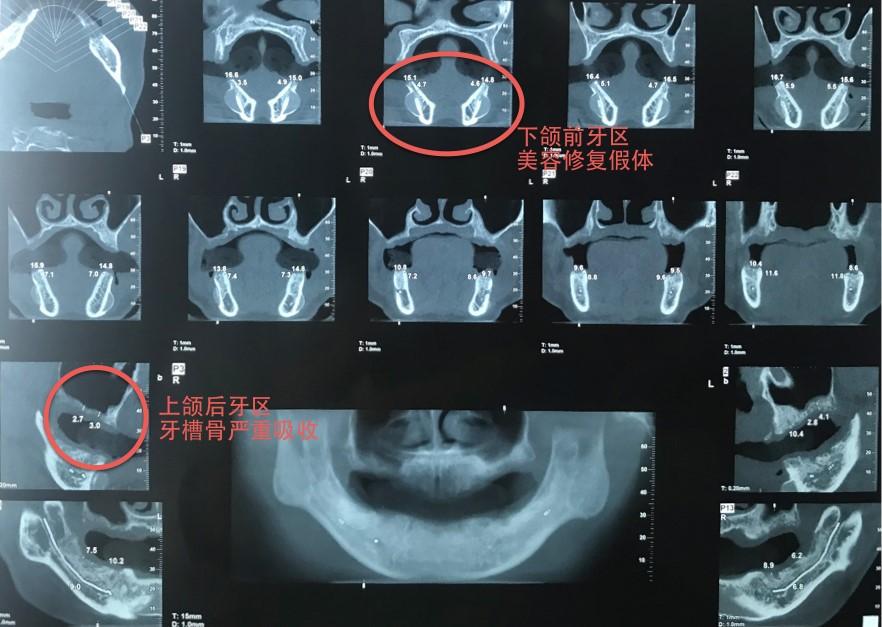

近日,南京醫(yī)科大學(xué)附屬口腔醫(yī)院暨江蘇省口腔醫(yī)院口腔種植科聯(lián)合口腔頜面外科完成一例復(fù)雜、疑難病例——全程數(shù)字化指導(dǎo)下的穿顴種植修復(fù)?;颊唏R女士,51歲,初來該院時(shí)由口腔種植科湯春波主任接診,檢查發(fā)現(xiàn)其口內(nèi)余留牙全部松動(dòng),牙結(jié)石覆蓋大部分牙面,已無法正常咀嚼,嚴(yán)重影響生活質(zhì)量,先指導(dǎo)其于該院口腔頜面外科拔除全部余留松動(dòng)牙。拔牙2個(gè)多月后,對(duì)患者重新進(jìn)行口內(nèi)及影像學(xué)檢查,CBCT顯示患者上頜牙槽骨嚴(yán)重缺損,右側(cè)后牙區(qū)可用骨高度不到3 mm,前牙區(qū)牙槽骨像雞蛋殼一樣薄、脆,而下頜前牙區(qū)還留有數(shù)年前的美容充填假體。在此基礎(chǔ)上進(jìn)行傳統(tǒng)種植,就如同在刀尖上行走,需要進(jìn)行繁復(fù)的植骨手術(shù),手術(shù)創(chuàng)傷極大。

術(shù)前CBCT檢查